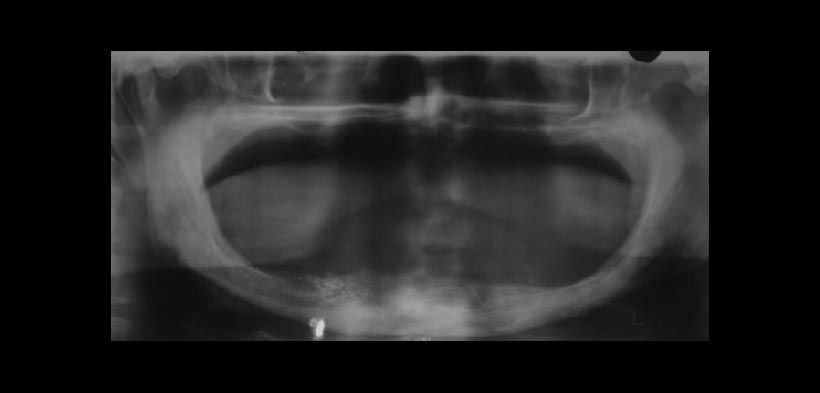

Las proyecciones de imágenes basadas en rayos x son de importancia para encontrar estas calcificaciones, basta con una radiografía panorámica más una exposición adicional como una radiografía oclusal para encontrar las calcificaciones (fig.1 y 2). La tomografía computarizada cone beam (CBCT) y la ecografía también tienen una sensibilidad alta al momento de encontrar calcificaciones en el tejido blando, e inmediatamente se busca una relación clínica directa para llegar al diagnóstico. Todos los casos de calcificación de los tejidos blandos deben ser sometidos a investigaciones para descartar desequilibrio de calcio-fósforo, insuficiencia renal e hiperparatiroidismo, como la insuficiencia renal es generalmente el punto de partida.

Fig. 1. Radiografía panorámica que muestra calcificaciones granulares en la región mandibular zona de premolares del lado derecho. Radiografía que pertenece a una paciente femenino de 65 años de edad con diagnóstico de insuficiencia renal crónico